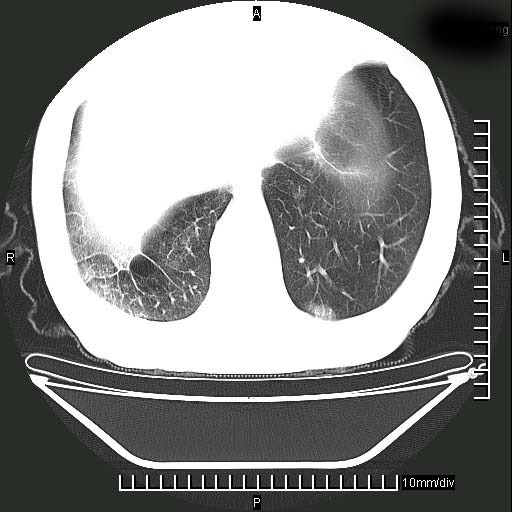

标题: CT24043:胸部增强:男性,60岁

既往肺结核,近10几天,咳嗽,咳痰,右侧胸痛,疼痛较明显,右上肺斑块考虑结核灶胸膜粘连,增强,可惜动脉期没有定好,未见强化,可延迟4分后又见较明显强化,中心见低密度影,如果说结核是边缘强化,可这个灶强化的面积挺大的,让人很挠头。

延迟4分后

[img][/img]